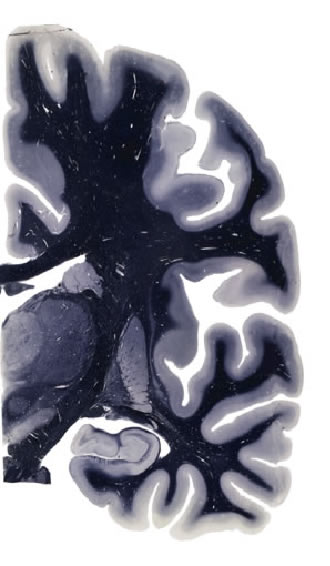

Frontal sections (Nissl) from the Atlas Brain: Gallery Slice Single

18,6 mm

Slice ID: r3-0702

Plate NR: ca 35-36

Position: 18,6 mm